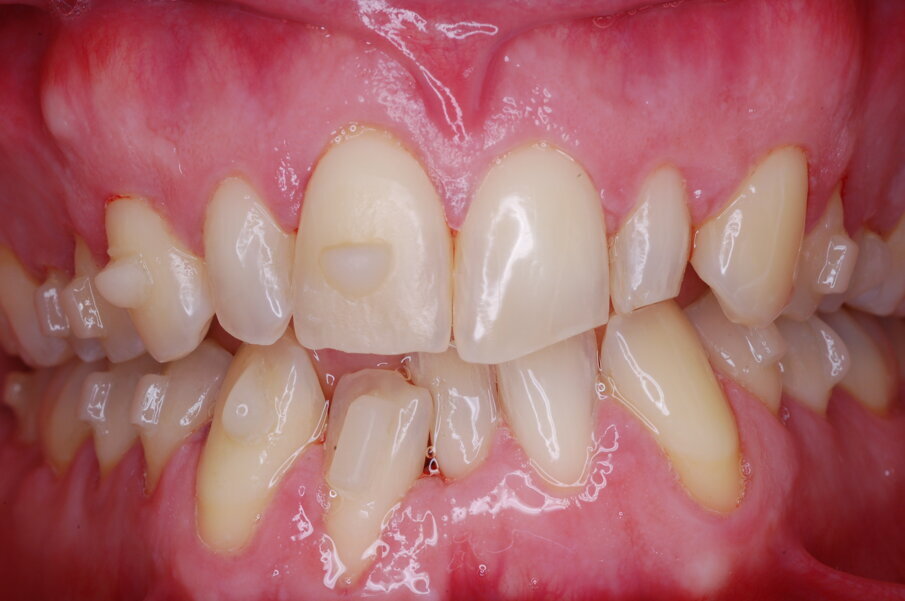

Diagnosi ed eziologia Un uomo sano di 39 anni si è presentato nel nostro studio ortodontico lamentando un aspetto dentale poco attraente e la paura della chirurgia ortognatica proposta da un altro ortodontista. Clinicamente, il profilo del paziente era rettilineo e la vista frontale non mostrava alcuna asimmetria facciale. L’esame funzionale non ha rivelato alcuna deviazione mandibolare o riduzione dei movimenti. Il paziente non aveva dolori articolari e non sono stati rilevati rumori articolari. Era presente una lieve occlusione molare bilaterale di Classe II, un morso aperto e un grave affollamento in entrambe le arcate. L’affollamento era particolarmente grave nell’arcata mandibolare, sebbene mancasse l’incisivo centrale mandibolare destro. Gli incisivi mascellari erano di piccole dimensioni, suggerendo una discrepanza dell’indice di Bolton se fossero stati presenti tutti e quattro gli incisivi mandibolari. Erano inoltre presenti un morso incrociato nella regione dell’incisivo laterale superiore sinistro e una grave rotazione distale del secondo premolare mandibolare sinistro (Figg. 1-8).

Figg. 1-8_Fotografie facciali e intraorali pre-trattamento.